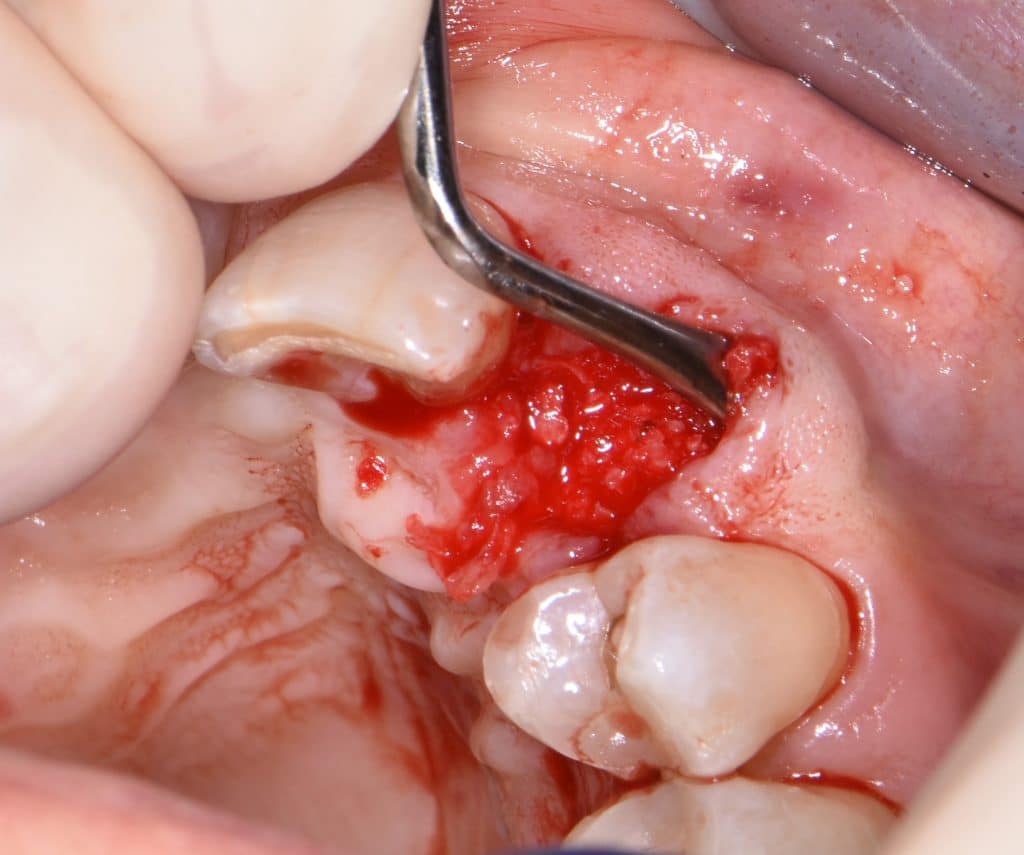

La pz N.G. di anni 52 (ASA 1) viene visitata nel mese di settembre 2017 per la mobilità ed inestetismo dell’elemento protesico 22, (foto iniziali sequenza 1) si evidenzia una frattura parziale della radice, si decide per l’estrazione ( foto sequenza 2) e sostituzione dell’elemento con un restauro implanto-protesico. Purtroppo la scarsa quota ossea apicale all’alveolo post-estrattivo (foto 2 rx) e l’alta valenza estetica dell’elemento ci rende cauti e si programma una socket preservation post estrattiva con l’ausilio delle membrane di prf (foto prf e socket sequenza 3 e 4). Durente i 5 mesi di guarigione la pz porta una protesi parziale mobile (foto 5,2) , a guarigione del sito post estrattivo si evidenzia una buona conservazione dei volumi osseo-gengivali,(foto guarigione sequenza 6) se pur presente una recessione distale all’elemnto 21.Nel mese di febbraio 2018 si procede all’inserimento di un impianto max-stability 3,75x12mm disegnando un lembo anticipato palatino per consentire un aumento dei tessuti vestibolari suturando con tecnica rool flap e trasformando l’elemento parziale mobile in una corona singola a carico immediato sul moncone temporameo applicando i concetti protesici bopt , (foto impianto moncone protesi provvisoria sequenza foto 7-8-9). Durante il periodo di maturazione dei tessuti molli vengono apportate opportune modifiche ai profili del provvisorio al fine di dare maggior spazio al tessuto gengivale, ( fotosequenza 10).Dopo circa 2 mesi dal protesizzazione provvisoria si è proceduto alla realizzazione del manufatto protesico con tecnica chair side sirona con l’ausilio del t-base (foto sequenza 11-12-13), realizzando in una sola seduta una corona in disilicato, ottenendo un risultato più che soddisfacente (Foto 14). Nel controllo a 3 mesi dal carico definitivo si apprezza la perfetta conservazione dei livelli ossei e gengivali. (foto sequenza 15).concludo con un follow up a 18 . Tengo a sottolineare che un caso come questo è stato conducibile con buoni risultati solo grazie alla piena fiducia della pz e alla sua massima motivazione e collaborazione. Ad oggi la pz sorride soddisfatta del risultato. E questo rappresenta la massima ricompensa di chi dedica tutto se stesso alla professione.